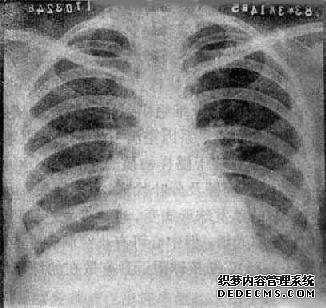

左下叶的硬组织可能会发炎。肺硬化可能与炎症有关,可能是由结核引起的,也可能与肿瘤有关。需要其他测试以确认诊断。

根据提供的问题,您可以去医院进行肺部CT扫描。该结果表明左下叶的硬组织更有可能发生。这时,建议去医院接受呼吸治疗,肺部CT或MRI。

如果您目前因呼吸困难发烧,建议进行肺活检以确定是否有占位性病变。

导致肺结节的原因很多:结合患者的特定病史和相关检查,对临床常见的炎性假瘤,钙化,结核和恶性肿瘤进行了全面的判断和分析。这是必要的。

如果很小,则可以定期观察。如果结节相对较大,建议考虑胸腔镜切除。